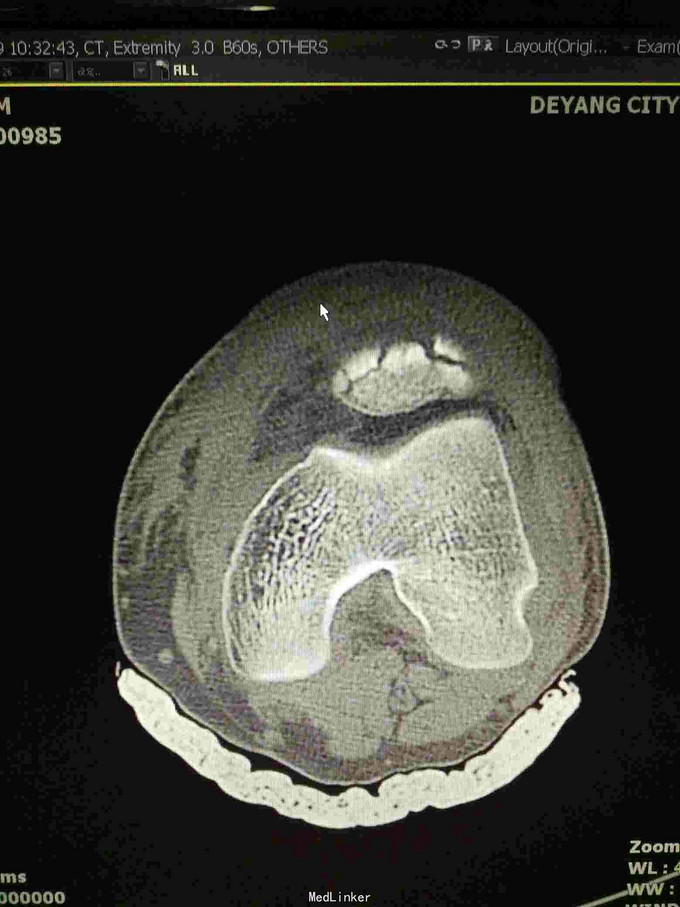

左髌骨粉碎性骨折

查体:左下肢活动受限,背伸障碍,左膝关节明显肿胀,压痛,扪及骨擦感,左足感觉及血循环可。 x片:左髌骨骨折。

诊断:左髌骨粉碎性骨折; 治疗,石膏固定,消肿止痛,行髌骨骨折切开复位克氏针内固定术,术中克氏针张力带钢丝固定,术后石膏固定。